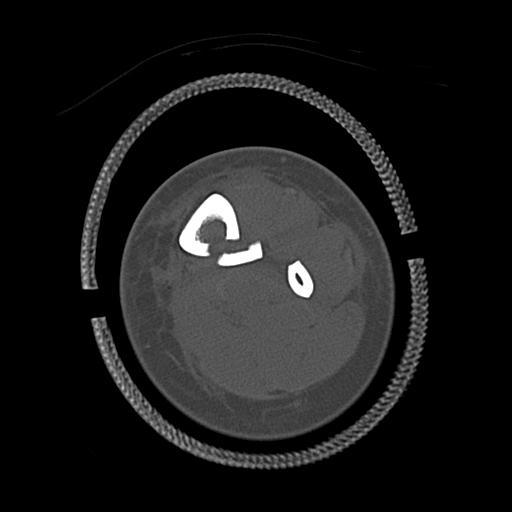

49554 3/13 膝 4R 3/16 4R 1/18 2R 78歳男性 膝蓋骨骨折